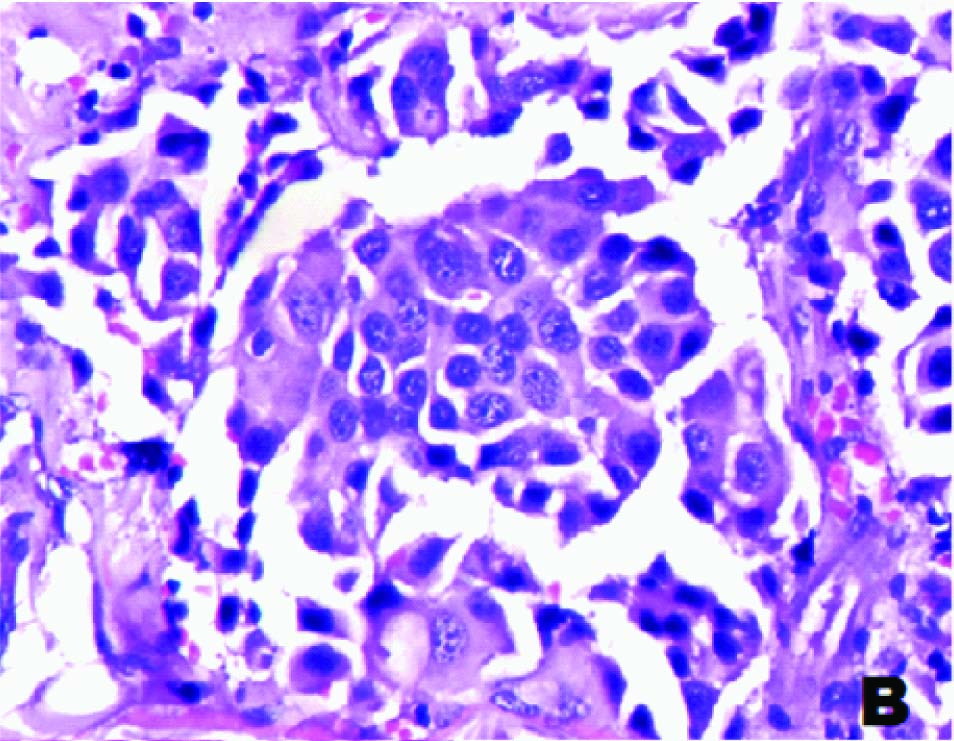

A 55-year-old male patient presented with pain abdomen and multiple skin nodules over the anterior abdominal wall and left cervical lymphadenopathy. On local examination, the abdominal skin nodules were firm to hard in consistency and the largest measured 3 x 2 cms. The left cervical lymph node was single, discrete and firm to hard in consistency. FNAC was performed on the abdominal skin nodules and the left cervical lymph node. FNAC smears studied from both the left cervical lymph node and the abdominal skin nodules showed similar cytological features. The smears were highly cellular and showed predominantly dispersed cell population of uniform tumour cells [Table/Fig-1a] in sheets, clusters, rosettes and tumour balls [Table/Fig-1b]. The cytoplasm was moderate, eosinophilic and granular. The nuclei were round to oval, with stippled chromatin and inconspicuous single prominent nucleolus [Table/Fig-1c]. Plenty of atypical mitoses were present [Table/Fig-1d]. In addition, many multinucleated giant cells and bizarre tumour cells were seen. Extracellular eosinophilic basement membrane- like material was also seen [Table/Fig-2a].

FNAC of skin nodule with tumour cells in rosettes (H&E, ×400)